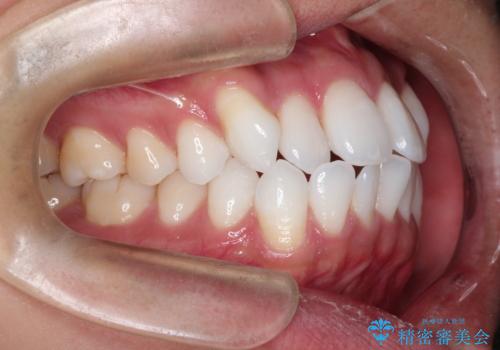

治療完了後、重なり合っていた歯はきれいに整い、懸念されていた前歯の突出も一切起こることなく、理想的な噛み合わせを実現しました。装置が目立ちにくかったため、治療期間中も周囲の目を気にすることなく、前向きに治療に取り組んでいただくことができました。